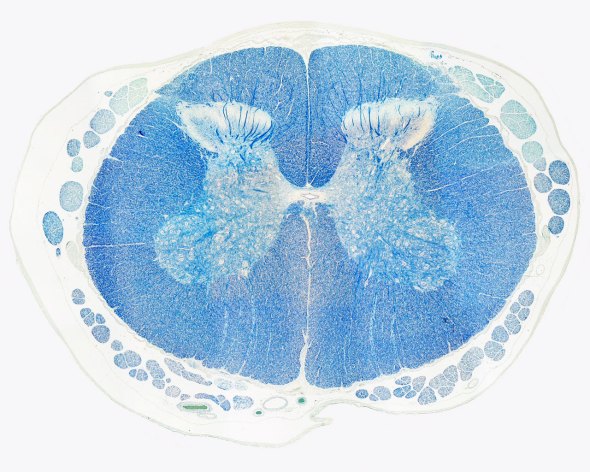

A human cervical spinal cord slice. Once you’ve read this post, you should be able to identify the major parts and tell which side is the front of the cord.